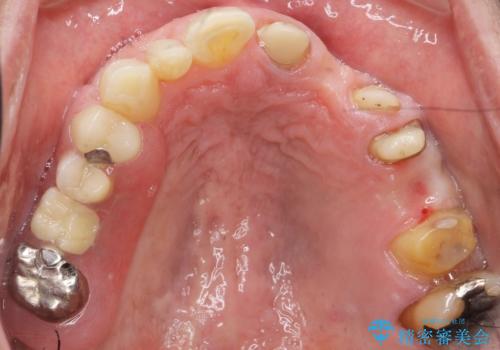

- ブリッジの支台歯であった左上の犬歯が折れたことを主訴に来院された患者様です。

犬歯は歯ぐきの奥深くまで割れており保存不可能な状態でしたが、どうしても抜きたくないとのことでした。

歯を牽引し健全歯質を歯肉縁上まで引き上げ、歯の保存を試みることにしました。

歯の牽引後、ブリッジの仮歯で保定しながら歯肉・骨の治癒を待ったのち、ブリッジによる補綴を行いました。